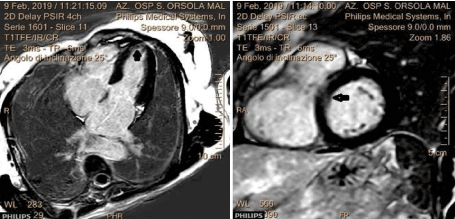

A 58-year-old female, with no prior medical history, presented to the ED for sudden nocturnal sharp chest pain radiated to the back. Her first ECG resulted quite normal (Figure 1), while blood analysis found out specific highly sensitive Troponin over normal limits (82 ng/L first check, then 400). Additionally, a fast echocardiogram showed marked hypokinesia at the mid-apical segment of left ventricular septal wall. She was immediately treated for Acute Coronary Syndrome (ACS) with beta-blocker, venitrin infusion, antiaggregant and anticoagulation therapy with pain relief and stable hemodynamics. Then, the patient was taken urgently to the catheterization lab where she was found to have to have a right hypoplastic coronary artery and a dominant left coronary artery free of atherosclerotic obstructive disease (Figure 2). The ECG of the day after (Figure 3), taken during the recovery in the cardiology department, showed significant changes in the ST-segment and T-wave in the precordial anteroseptal leads which suggested ischemia. Anyway, a few days later she was discharged in good health from the hospital with a diagnosis of suspected myocarditis. A follow-up ECG done at the GP's office (Figure 3) showed that the significant changes recorded in the cardiology department were more accentuated, confirming ST-segment elevation and Negative T-waves in the precordial anteroseptal leads. Also, a TTE confirmed a slight anteroseptal hypokinesis. Subsequently, 15 days later a CMR was performed to rule out myocarditis or other pathologies with myocardial damage, as both cardiologists and GP's have suspected. However, radiologists reported that no signs of myocarditis were shown by the CMR and there was no mention of myocardial damage like oedema or scar or signs of microvascular obstruction (MVO), even though some images (Figure 4) could suggest oedema on the Antero-mid-septal and apical wall suitable for microvascular obstruction compatible with the ECG findings and clinical presentation.

Figure 4. CMR findings that showed a spot of microvascular obstruction (MVO) in anteroseptal and apical wall.

The discussion aims to highlight the diagnostic difficulties that regard this novel syndrome despite the fact the clinical criteria are well defined and established. Vascular dysfunction without obstructive coronary disease is more prevalent in women and associated with increased use of healthcare resources, higher symptom burden, and importantly 2-fold higher mortality, indicating that non-obstructive coronary disease is not always a benign condition [7,8].  Simply put, this case describes the presentation of acute myocardial infarction with ECG changes and troponin positivity without obstructive coronary artery disease and with CMR not diriment for MINOCA syndrome.  In fact, as clinical history demonstrates, the patient was first admitted to the emergency department for signs of an acute coronary syndrome that was promptly suspected for the rise of specific troponin, and for the echocardiographic finding of hypokinesia of the mid and apical segment septal wall, even though the ECG resulted apparently normal. Consequently, the patient was taken to the hemodynamic laboratory to undergo her to coronary angiography, which however showed epicardial coronary arteries free from obstructive disease. The next inpatient cardiology period ran regularly and after a few days, the patient was discharged from the hospital with the diagnosis of suspected myocarditis. However, the follow-up ECG showed clear changes when compared to the ECGs performed in the ED and cardiology department, showing an ECG epicardial pattern of anteroseptal wall ischemia. A subsequent cardiac magnetic resonance imaging (CMR) performed 15 days after the onset of the symptoms appeared at first negative reading for myocarditis and indicated just a slight dilatation of the left cardiac chambers. Even so, an in-depth view of the CMR images showed some suggestive aspects on the apical septal wall compatible with minimal myocardial damage with isolated MVO spots. It is therefore plausible that the patient had MINOCA cardiac syndrome (i.e. coronary spasm, partial occlusion quickly revascularized, etc.) without serious consequence thanks to the prompt drug therapy performed.  The diagnostic and prognostic impact of cardiovascular magnetic resonance imaging plays a key role in assessing patients with suspected myocardial infarction with unobstructed coronary arteries. Therefore, CMR is strongly recommended by various experts and the ESC's task force when evaluating patients with the working diagnosis of MINOCA. In any case, CMR is recommended within 7 days of presentation because delayed imaging can sometimes result in some features no longer being evident [9].